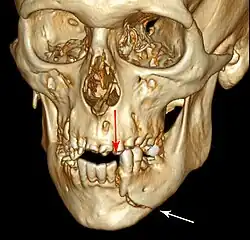

3D CT of mandible fracture.

This injury involves the alveolar bone and may extend beyond the alveolus.[5][6] There are five different types of alveolar fractures:

Trauma injuries involving the alveolus can be complicated as it does not happen in isolation, very often presents along with other types of tooth tissue injuries.

Signs of dentoalveolar fracture:

• Change to occlusion

• Multiple teeth moving together as a segment and are normally displaced

• Bruising of attached gingivae

• Gingivae across the fracture line often lacerated

Investigation: Require more than one radiographic view to identify the fracture line.

Treatment: Reposition displaced teeth under local anaesthetic and stabilise the mobile segment with a splint for 4 weeks, suture any soft tissue lacerations.